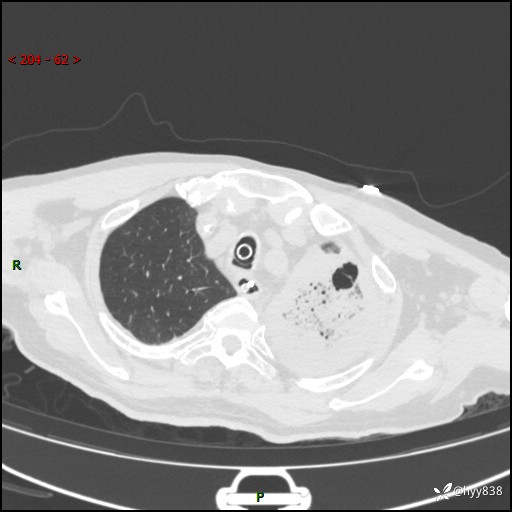

胸部CT复查(2024.8.5)